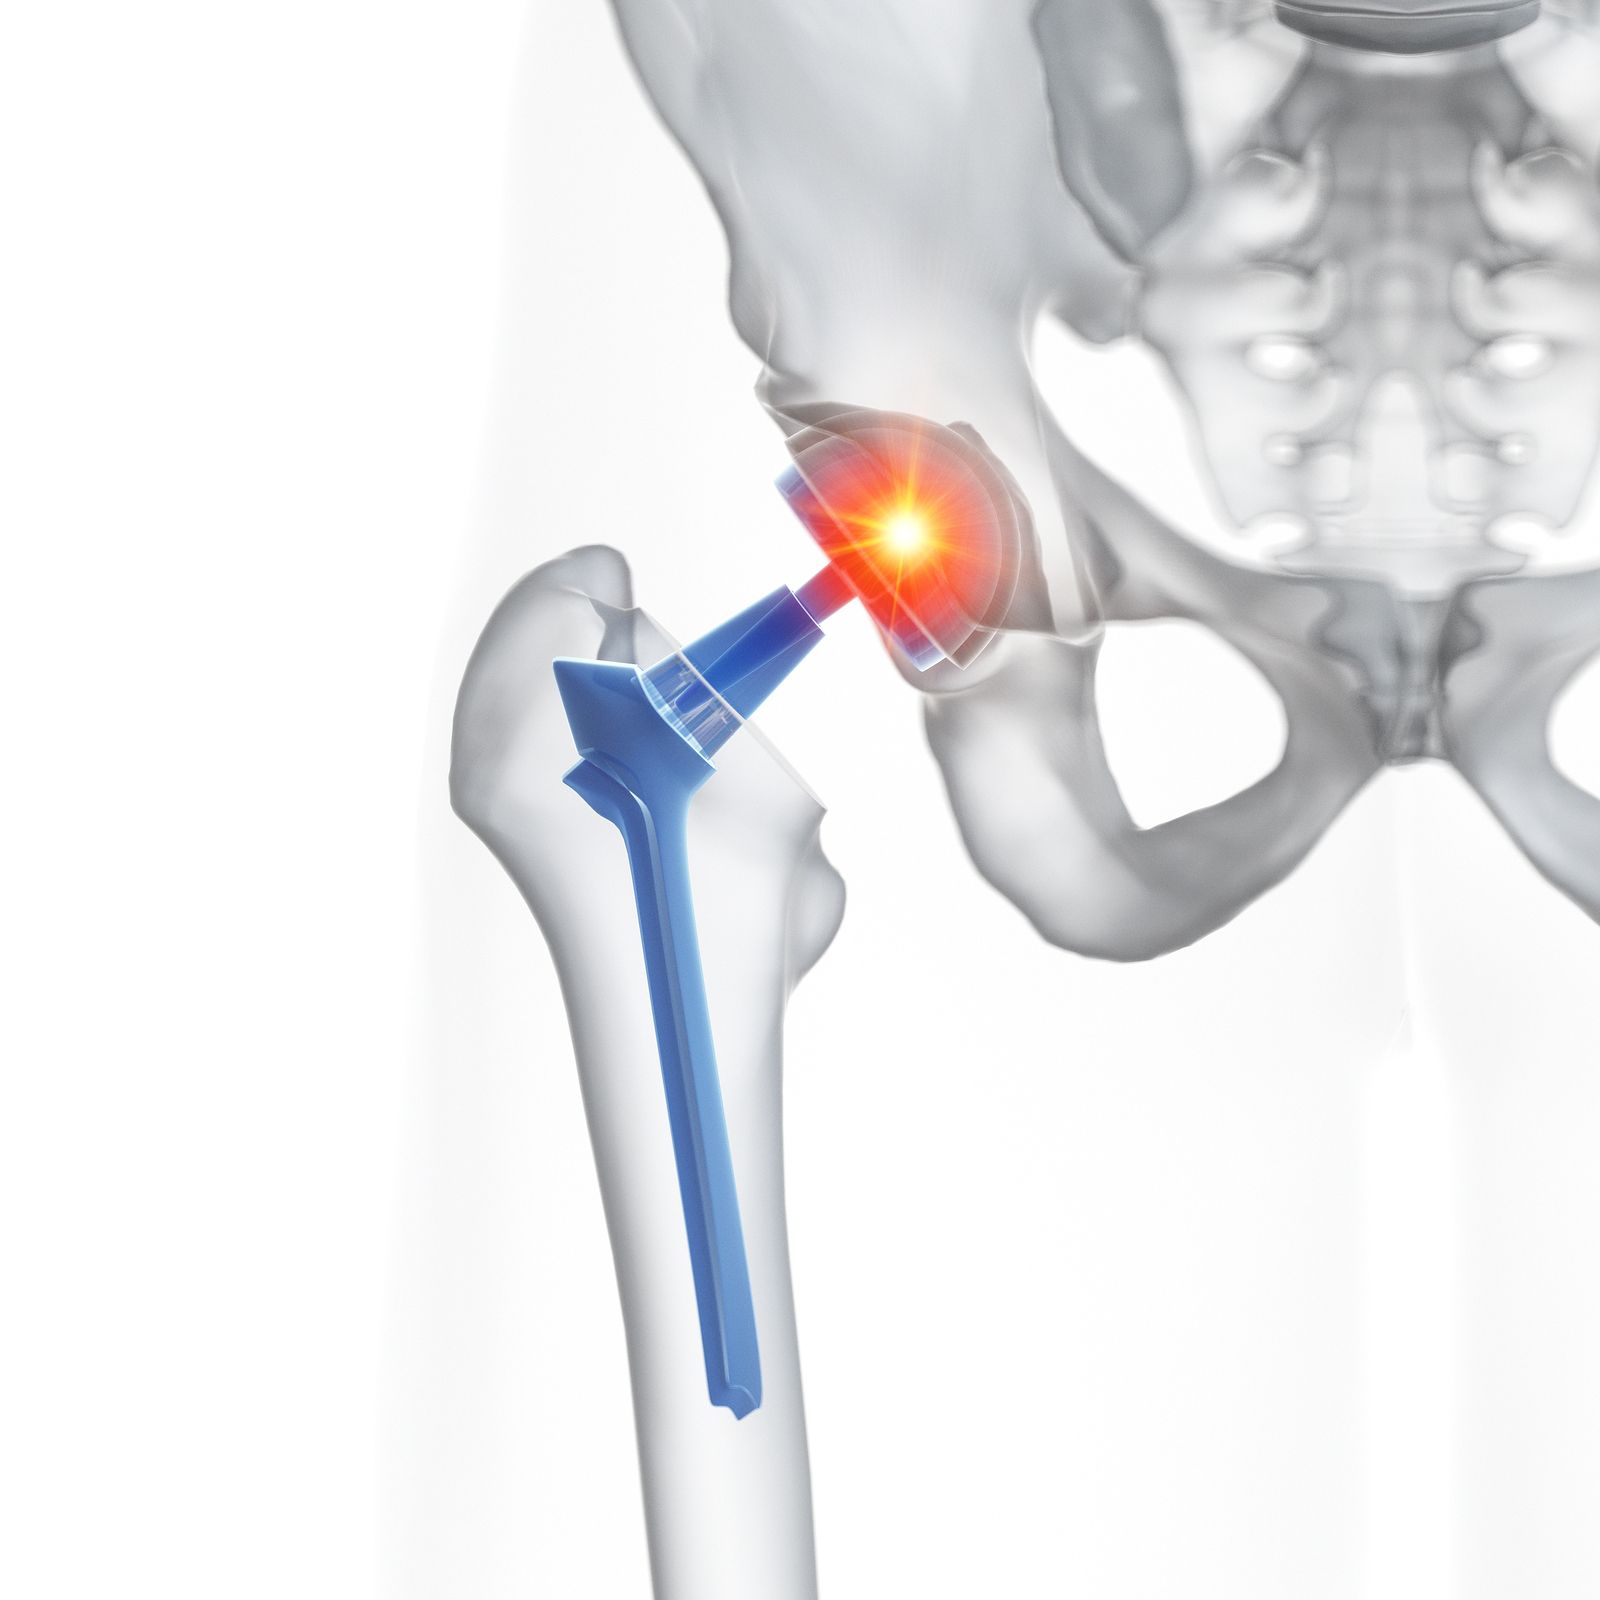

Duración del tratamiento antibiótico en la infección de prótesis articular

En un ensayo clínico aleatorizado se encontró que un tratamiento antibiótico acortado a seis semanas tuvo peores resultados que el convencional de 12 semanas de duración. New England Journal of Medicine, 27 de mayo de 2021.

Infección de prótesis articular: qué hacer cuando no se puede operar

El tratamiento antibiótico supresor prolongado podría ser eficaz en pacientes ancianos en los que la opción quirúrgica no es una alternativa. European Journal of Clinical Microbiology & Infectious Diseases, abril de 2017